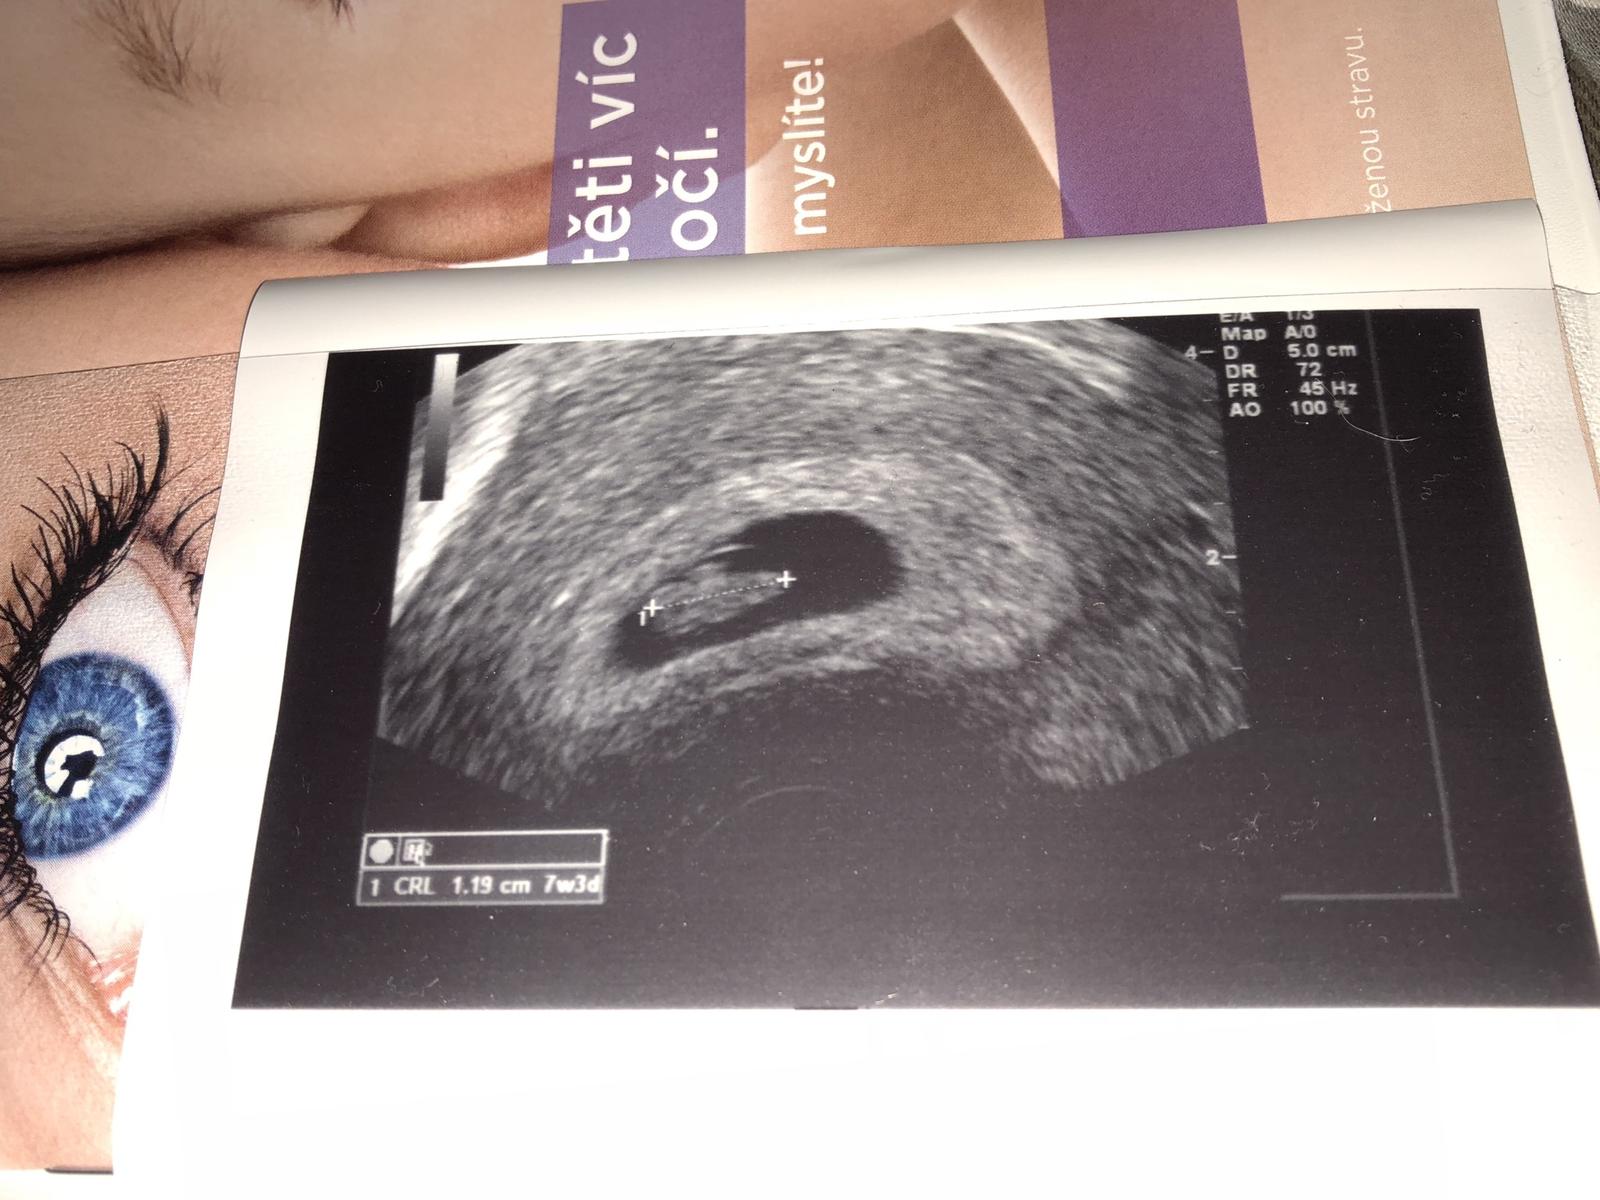

@merilina jupíííí...je tam...:o))) kolik měří? 1,19?

@rosalline jj, 1,19 😉

@merilina už ho vidím a kolikátý týden podle ultrazvuku jsi? A co srdíčko pustili ti ho?

@fanunka Podle Utz 7+3.... nepustili 😒

@merilina uzasna fotka.. uplne se vracim do doby kdy sem si taky odnasela prvni fotecku a ted tu mam dnes presne mesicni mimi ... gratulace